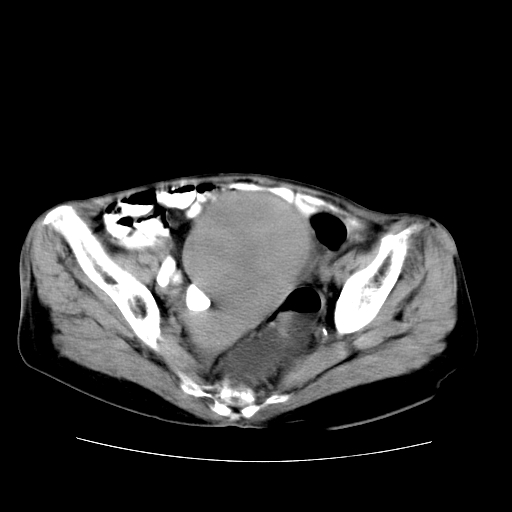

女性,72岁。

主诉下腹部坠痛不适1年余。

子宫增大如孕3月大小,质软,活动可,无压痛。

b超提示:盆腔(子宫前方)低回声团块。

临床诊断:盆腔肿块查。

1、这个肿瘤密度均匀,增强后轻中度均匀性强化,与左侧附件关系密切,肿瘤边缘光整、清晰。

2、左侧卵巢增大呈8×8×10cm大小,实性,表面光滑,边清,左侧输卵管爬行于左卵巢上,子宫萎缩。右输卵管、卵巢萎缩。

3、病理号:092658

左侧卵巢纤维瘤(性索间质肿瘤)

卵巢纤维瘤为良性卵巢性索间质肿瘤,常为单侧发病,当合并腹水或胸腹水时称麦格斯(meigs)综合征,肿瘤切除后胸腹水可消失。ct表现为盆腔内边界清楚的圆形或椭圆形肿块,常有分叶或不规则;肿瘤多为实性,少数为囊性、囊实性,完全囊性者可见壁结节。实性部分与子宫等密度;增强扫描常为轻度强化或几乎不强化。